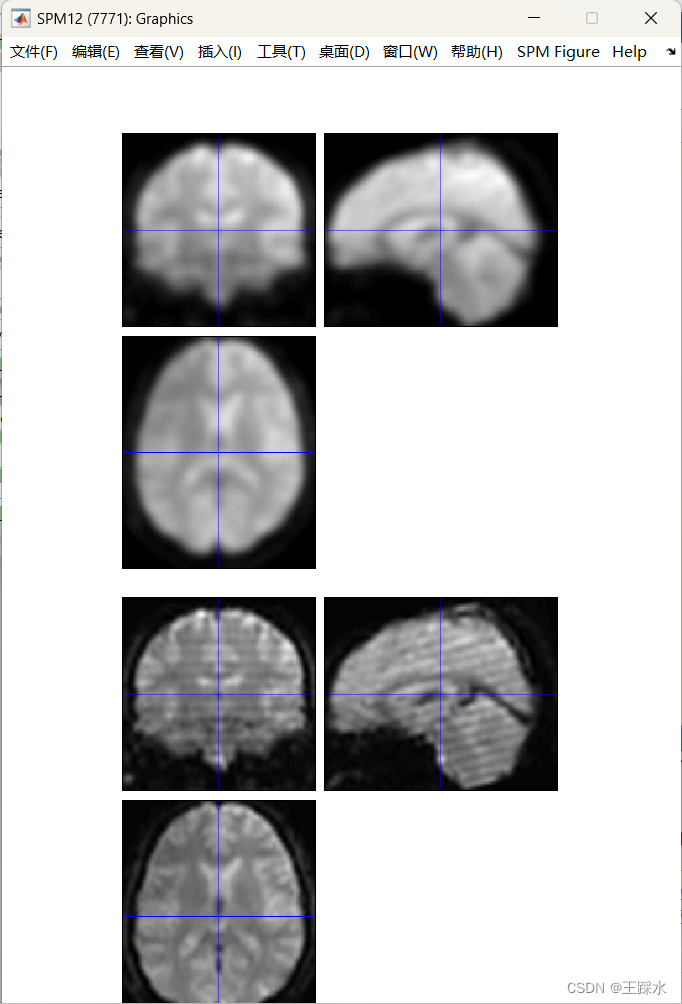

4、空间平滑

两个原因:降低噪音、提高信噪比,在相邻的体素之间做空间平滑,他们的信号噪音程度是随机变化的,平滑后,噪音相互抵消,提高信噪比;平滑后,激活脑区的范围更大,大脑形状不一样,平滑后会让激活脑区重合度更高一些。

FHWM指的是空间平滑kernel大小:高斯分布最高点一半的曲线的宽度,用了默认的8

Ta da!